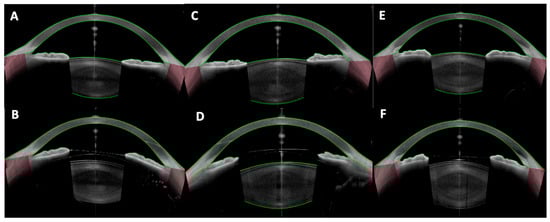

Beyond phakic refractive lenses, OCT has significant utility in secondary IOL fixations—cases where an intraocular lens is implanted in an eye without capsular support. This includes scleral-fixated IOLs (both sutured and sutureless Yamane-type), Carlevale lenses (a one-piece lens with T-shaped scleral anchoring plugs), iris-claw lenses used for aphakia, and other innovative techniques [46,47,48,49,50] (Figure 6 and Figure 7). These scenarios present unique imaging challenges, as the IOL is often located in the posterior chamber or at the iris plane, and the supports (haptics, flanges, or sutures) are not within the visible pupil.

Figure 7. Anterior segment optical coherence tomography images showing a well-positioned Carlevale sutureless scleral-fixated intraocular lens with (A) vertical and (B) horizontal cross-sectional scans demonstrating central optic positioning, slight tilt, and adequate distance from the corneal endothelium and iris plane. (C,D) Images show both haptics of the Carlevale lens anchored within intrascleral tunnels approximately 1.5–2.0 mm posterior to the limbus.